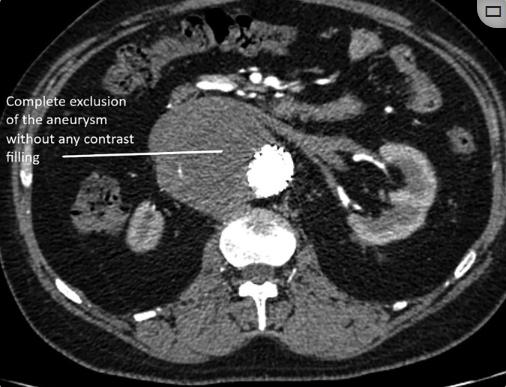

每六个月对病人进行一次CT主动脉造影随访。在两次为期两年的随访中,CT血管造影显示腹主动脉囊状动脉瘤因IB型内漏而增大(图3)。内漏是由于肾下主动脉疾病的远端进展。通过在远端部署28×28×100 TAA支架移植物对其进行管理(图4)。通过部署6×27mm支架来加固左肾支架。术后主动脉造影证实动脉瘤被排除,SMA和左肾动脉血流通畅。后续CT显示动脉瘤段完全排除(图5)。患者每天服用75毫克阿司匹林、抗高血压药、口服泼尼松龙和托法替尼。

图5、后续CT。腹主动脉囊状动脉瘤的完全闭塞